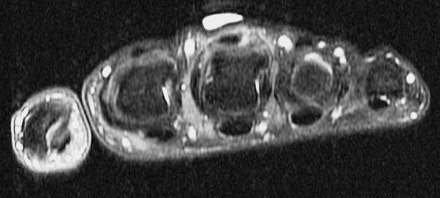

Figure 4 for case Boxers knuckle

Figure 4